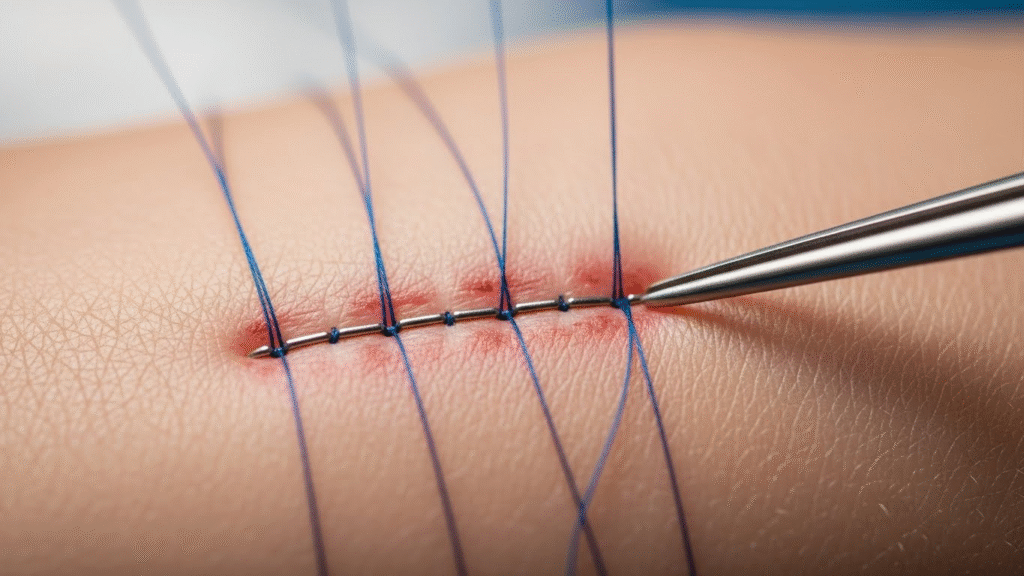

4️⃣ Stitches to Prevent New Pockets

Closing the skin properly reduces future buildup.